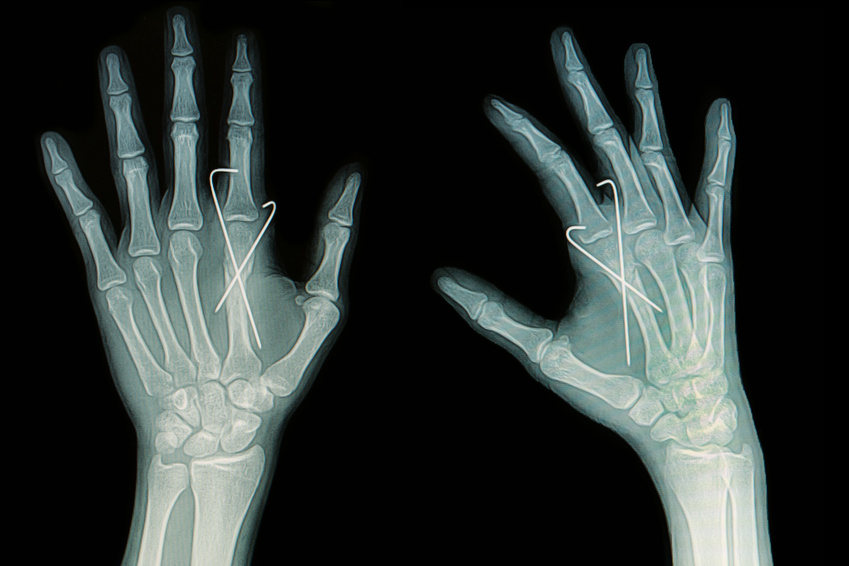

A range of hand, wrist and elbow injuries and conditions are seen at Total Hand & Upper Limb Therapy.

These can be fractures and dislocations, nerve compression problems, tendon overuse problems as well as problems relating to trauma of the upper limb.